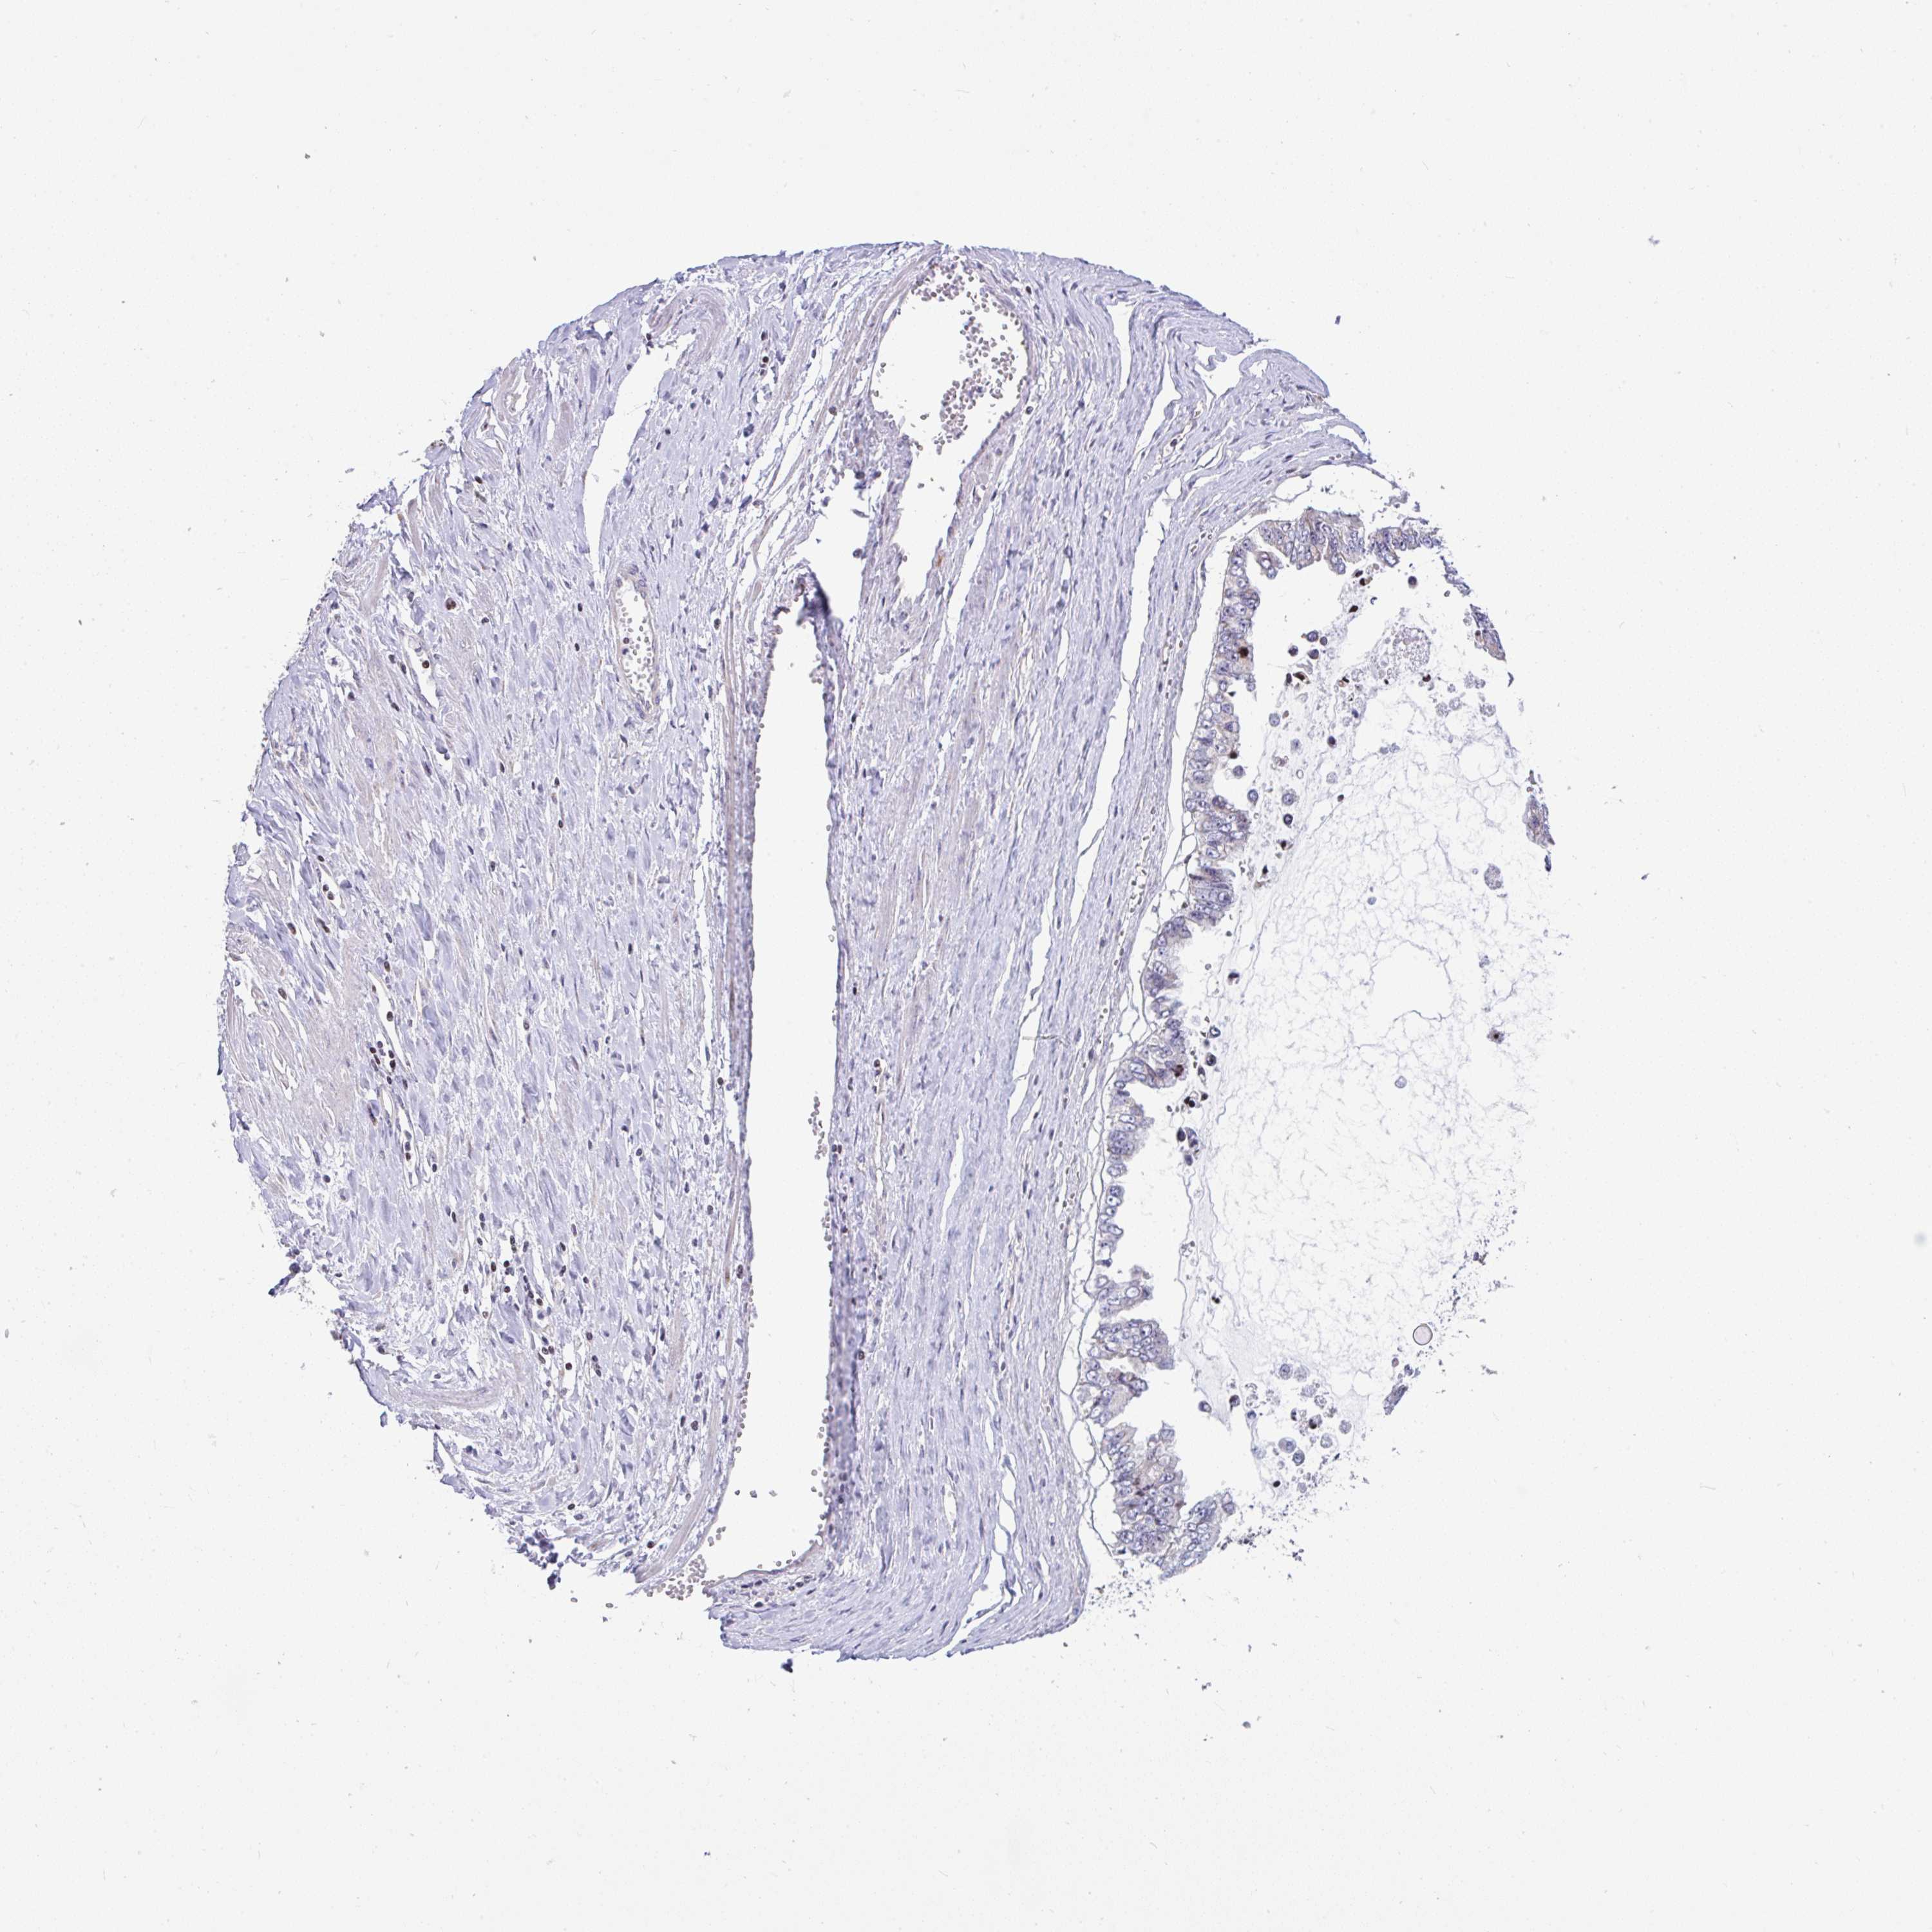

OVARIAN CANCER - Protein expressioni

A mouse-over function shows sample information and annotation data. Click on an image to view it in a full screen mode. Samples can be filtered based on level of antibody staining by selecting one or several of the following categories: high, medium, low and not detected. The assay and annotation is described here.

Note that samples used for immunohistochemistry by the Human Protein Atlas do not correspond to samples in the TCGA dataset.

Antibody stainingi

Antibody staining in the annotated cell types in the current human tissue is reported as not detected, low, medium, or high, based on conventional immunohistochemistry profiling in selected tissues. This score is based on the combination of the staining intensity and fraction of stained cells.

Each image is clickable and will lead to virtual microscopy that enables deeper exploration of all samples and also displays staining intensity scores, fraction scores and subcellular localization as well as patient and tissue information for each sample.

Antibody HPA055542

Cystadenocarcinoma, serous, NOS

Cystadenocarcinoma, mucinous, NOS

Carcinoma, endometroid